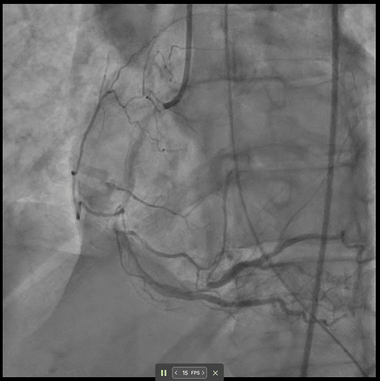

A 69-year-old woman presented with cardiac arrest and inferior STEMI on initial ECG which subsequently normalised. Despite an angiographically patent RCA and resolved ST-elevation, DeepRV flagged reduced RV function. Six hours later she deteriorated, requiring vasopressors; TTE confirmed acute RV failure. After RCA stenting, the DeepRV score normalised — illustrating real-time detection of reversible RV dysfunction beyond standard angiographic assessment.